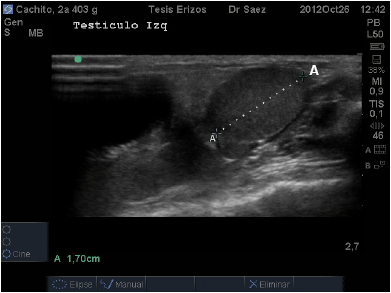

Topográficamente los testículos de los ETA se encuentran intra abdominales, vía ecográfica se observan caudo-ventralmente en el abdomen caudal y ubicados dentro de los recesos para-anales. El órgano presentó forma circular en el corte transverso, en la parte media, a diferencia del corte longitudinal donde se observaron ovalados. Su eje largo presentó una ligera oblicuidad siendo dorso-craneal/caudo-ventral. Su parénquima se presentó de mediana ecogenicidad, granulado fino y homogéneo. No se visualizó la línea ecogénica que describió Nyland [7] en el interior del testículo de animales domésticos, que correspondería al mediastino testicular (FIG. 4), esto podría deberse a que probablemente el mediastino en esta especie es menos fibroso o podría ser menos desarrollado y ubicarse en el extremo craneal del testículo, tal como ocurre en el equino (Equus caballus). Sería recomendable realizar un estudio morfoestructural para confirmar esta observación.

Los resultados cuantitativos de morfometría fueron medidos en centímetros (cm) y expresados en promedios junto con desviación estándar (X ± DE). Se midió ancho, alto y largo de Testículo Izquierdo, y Testículo Derecho. En el caso del Epidídimo se midió ancho y alto de epidídimo en diez machos, ya que en uno de los pacientes no fue observable. En el 80% de los casos en el epidídimo predominó el ancho sobre el largo. Se midió el ancho, alto y largo de la Próstata. Los resultados se especifican en la TABLA III.